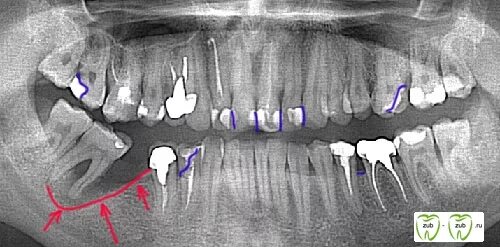

Удалить зубы семерки